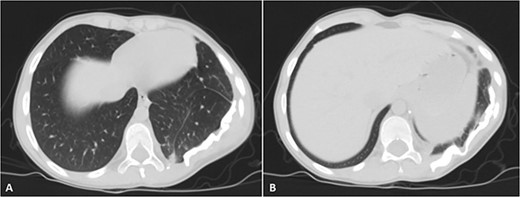

Selected axial CT images with mediastinal windowing showing multiple cuts of the patient’s chest. A huge relatively well-defined heterogeneous mass lesion is noted occupying the left lower hemi-thorax causing left lung volume loss and significant rightward mediastinal shift. No definite invasion of the adjacent ribs, however, remodeling of the lower aspect of the left posterior tenth rib is noted with the widening of the left tenth intercostal space and involvement of the left erector spinae muscles by the previously mentioned mass.